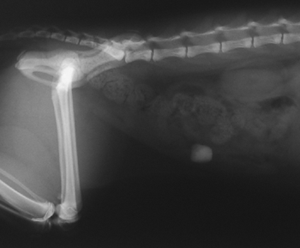

Chat ayant avalé un caillou

Herbe à chats

(Figure : vetopsy.fr)

Le dernier cas est une première pour moi : un chat ayant avalé un caillou, ce qui est extrêmement rare.